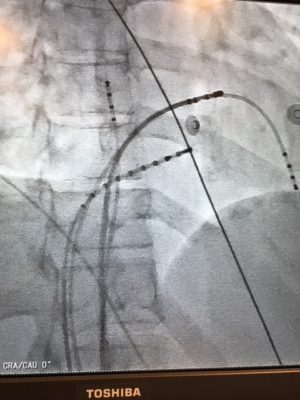

Thirty minutes later, I found myself barely conscious lying in some ski hut with an IV in my muddy arm, surrounded by shouting paramedics. I was in SVT or supraventricular tachycardia. I’d had these episodes of severely fast heart beat of 200 beats per minute since I was 14, but I’d always been able to make them go away on their own. Not this time. This time I needed a drug called adenosine to essentially restart my heart to reset the normal electrical rhythm.

Needless to say, I was pretty freaked out by it all. I saw a cardiologist. My options were 1) Do nothing 2) Take beta blocker drugs everyday and feel like garbage 3) Have an ablation surgery to burn out the extra electrical pathway I have in my heart.

My birth experience is what finally gave me the courage to do the heart ablation surgery. It’s now August 2018, and it’s been a week since the surgery. Waiting in anticipation for this heart surgery – a procedure where I’d have to be awake, and one that could leave me with a pacemaker at 36 years old – was the scariest thing I’ve ever experienced.